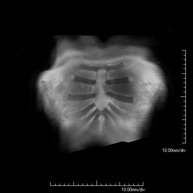

Prueba diagnóstica no invasiva que consiste en la obtención de imágenes de alta definición anatómica de las arterias cerebrales mediante el empleo de un campo electromagnético y ondas de radio (con un emisor y un receptor). No utiliza radiación ionizante. En la mayoría de los casos es necesario el empleo de contraste paramagnético (Gadolinio). Permite un estudio angiográfico no invasivo gracias a la inyección de Gadolinio con posterior reconstrucción en 2D y 3D, gracias a estaciones de trabajo especializadas. Indicaciones: malformaciones vasculares, aneurismas de arterias cerebrales, arteriosclerosis. - Angio-RM troncos supraaórticos

Prueba diagnóstica no invasiva que consiste en la obtención de imágenes de alta definición anatómica de las arterias cerebrales, mediante el empleo de un campo electromagnético y ondas de radio (con un emisor y un receptor). No utiliza radiación ionizante. En la mayoría de los casos es necesario el empleo de contraste paramagnético (Gadolinio). Permite un estudio angiográfico no invasivo gracias a la inyección de Gadolinio con posterior reconstrucción en 2D y 3D, gracias a estaciones de trabajo especializadas. Indicaciones: Malformaciones vasculares, aneurismas de arterias cerebrales, arteriosclerosis. - Angio-RM Troncos supraaórticos